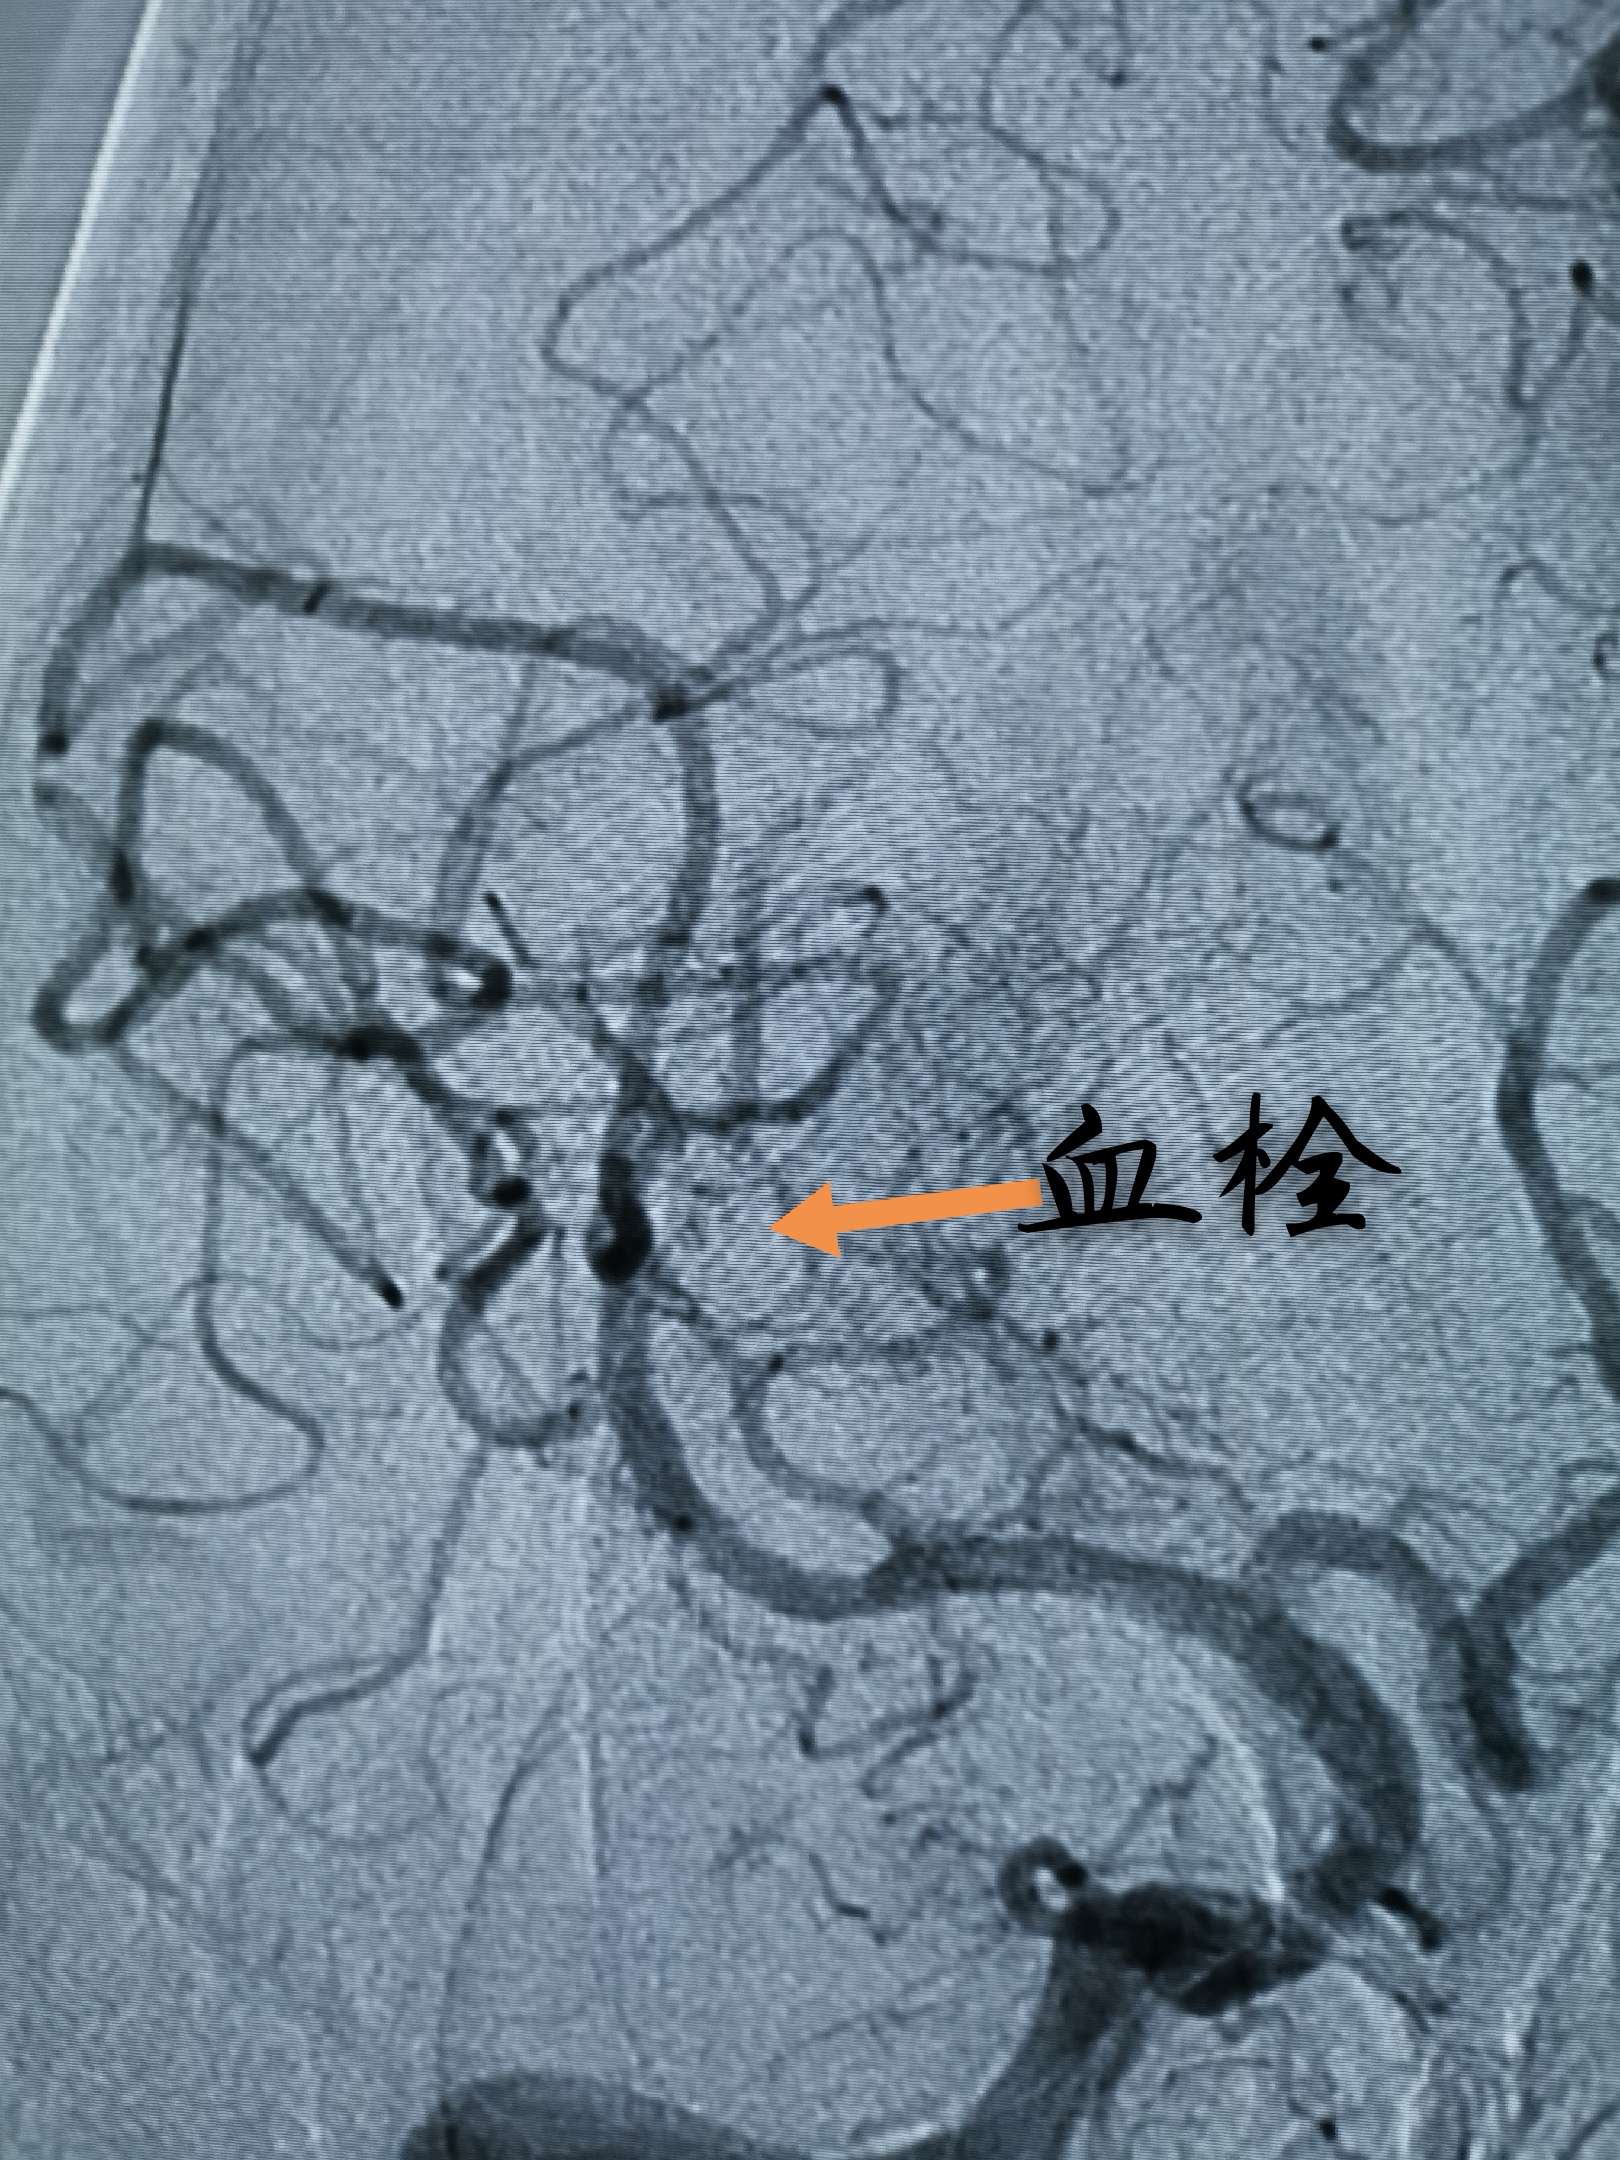

微导管造影发现血栓碎裂,并向远端逃逸

再次Guiding内造影,发现M3另一分支内仍有碎裂后逃逸的血栓